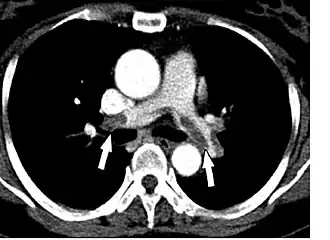

![]() КТ-картина тромбоэмболии главных лёгочных артерий при КТ-ангиопульмонографии. | |

КТ-ангиопульмонография позволяет обнаружить тромбы в лёгочной артерии. При данном методе датчик вращается вокруг больного, которому предварительно вводится внутривенно контрастный препарат. В результате создаётся объёмная картина лёгких. Однако пациент должен суметь задержать дыхание во время процедуры (несколько секунд). Метод менее инвазивен и более безопасен, чем ангиография[10]. По мнению экспертов Европейского общества кардиологов у больных высокого риска достаточно однодетекторной КТ для подтверждения или исключения ТЭЛА. У больных невысокого риска рекомендуют мультидетекторную КТ, так как она позволяет более чётко выявить тромбы в ветвях лёгочной артерии[18].